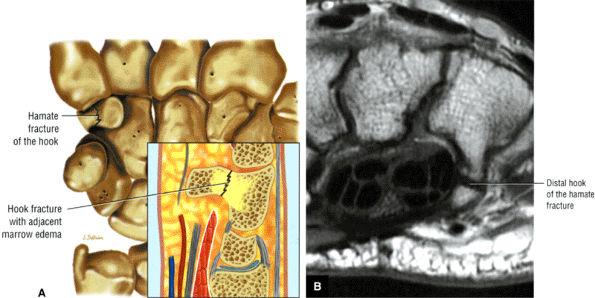

|